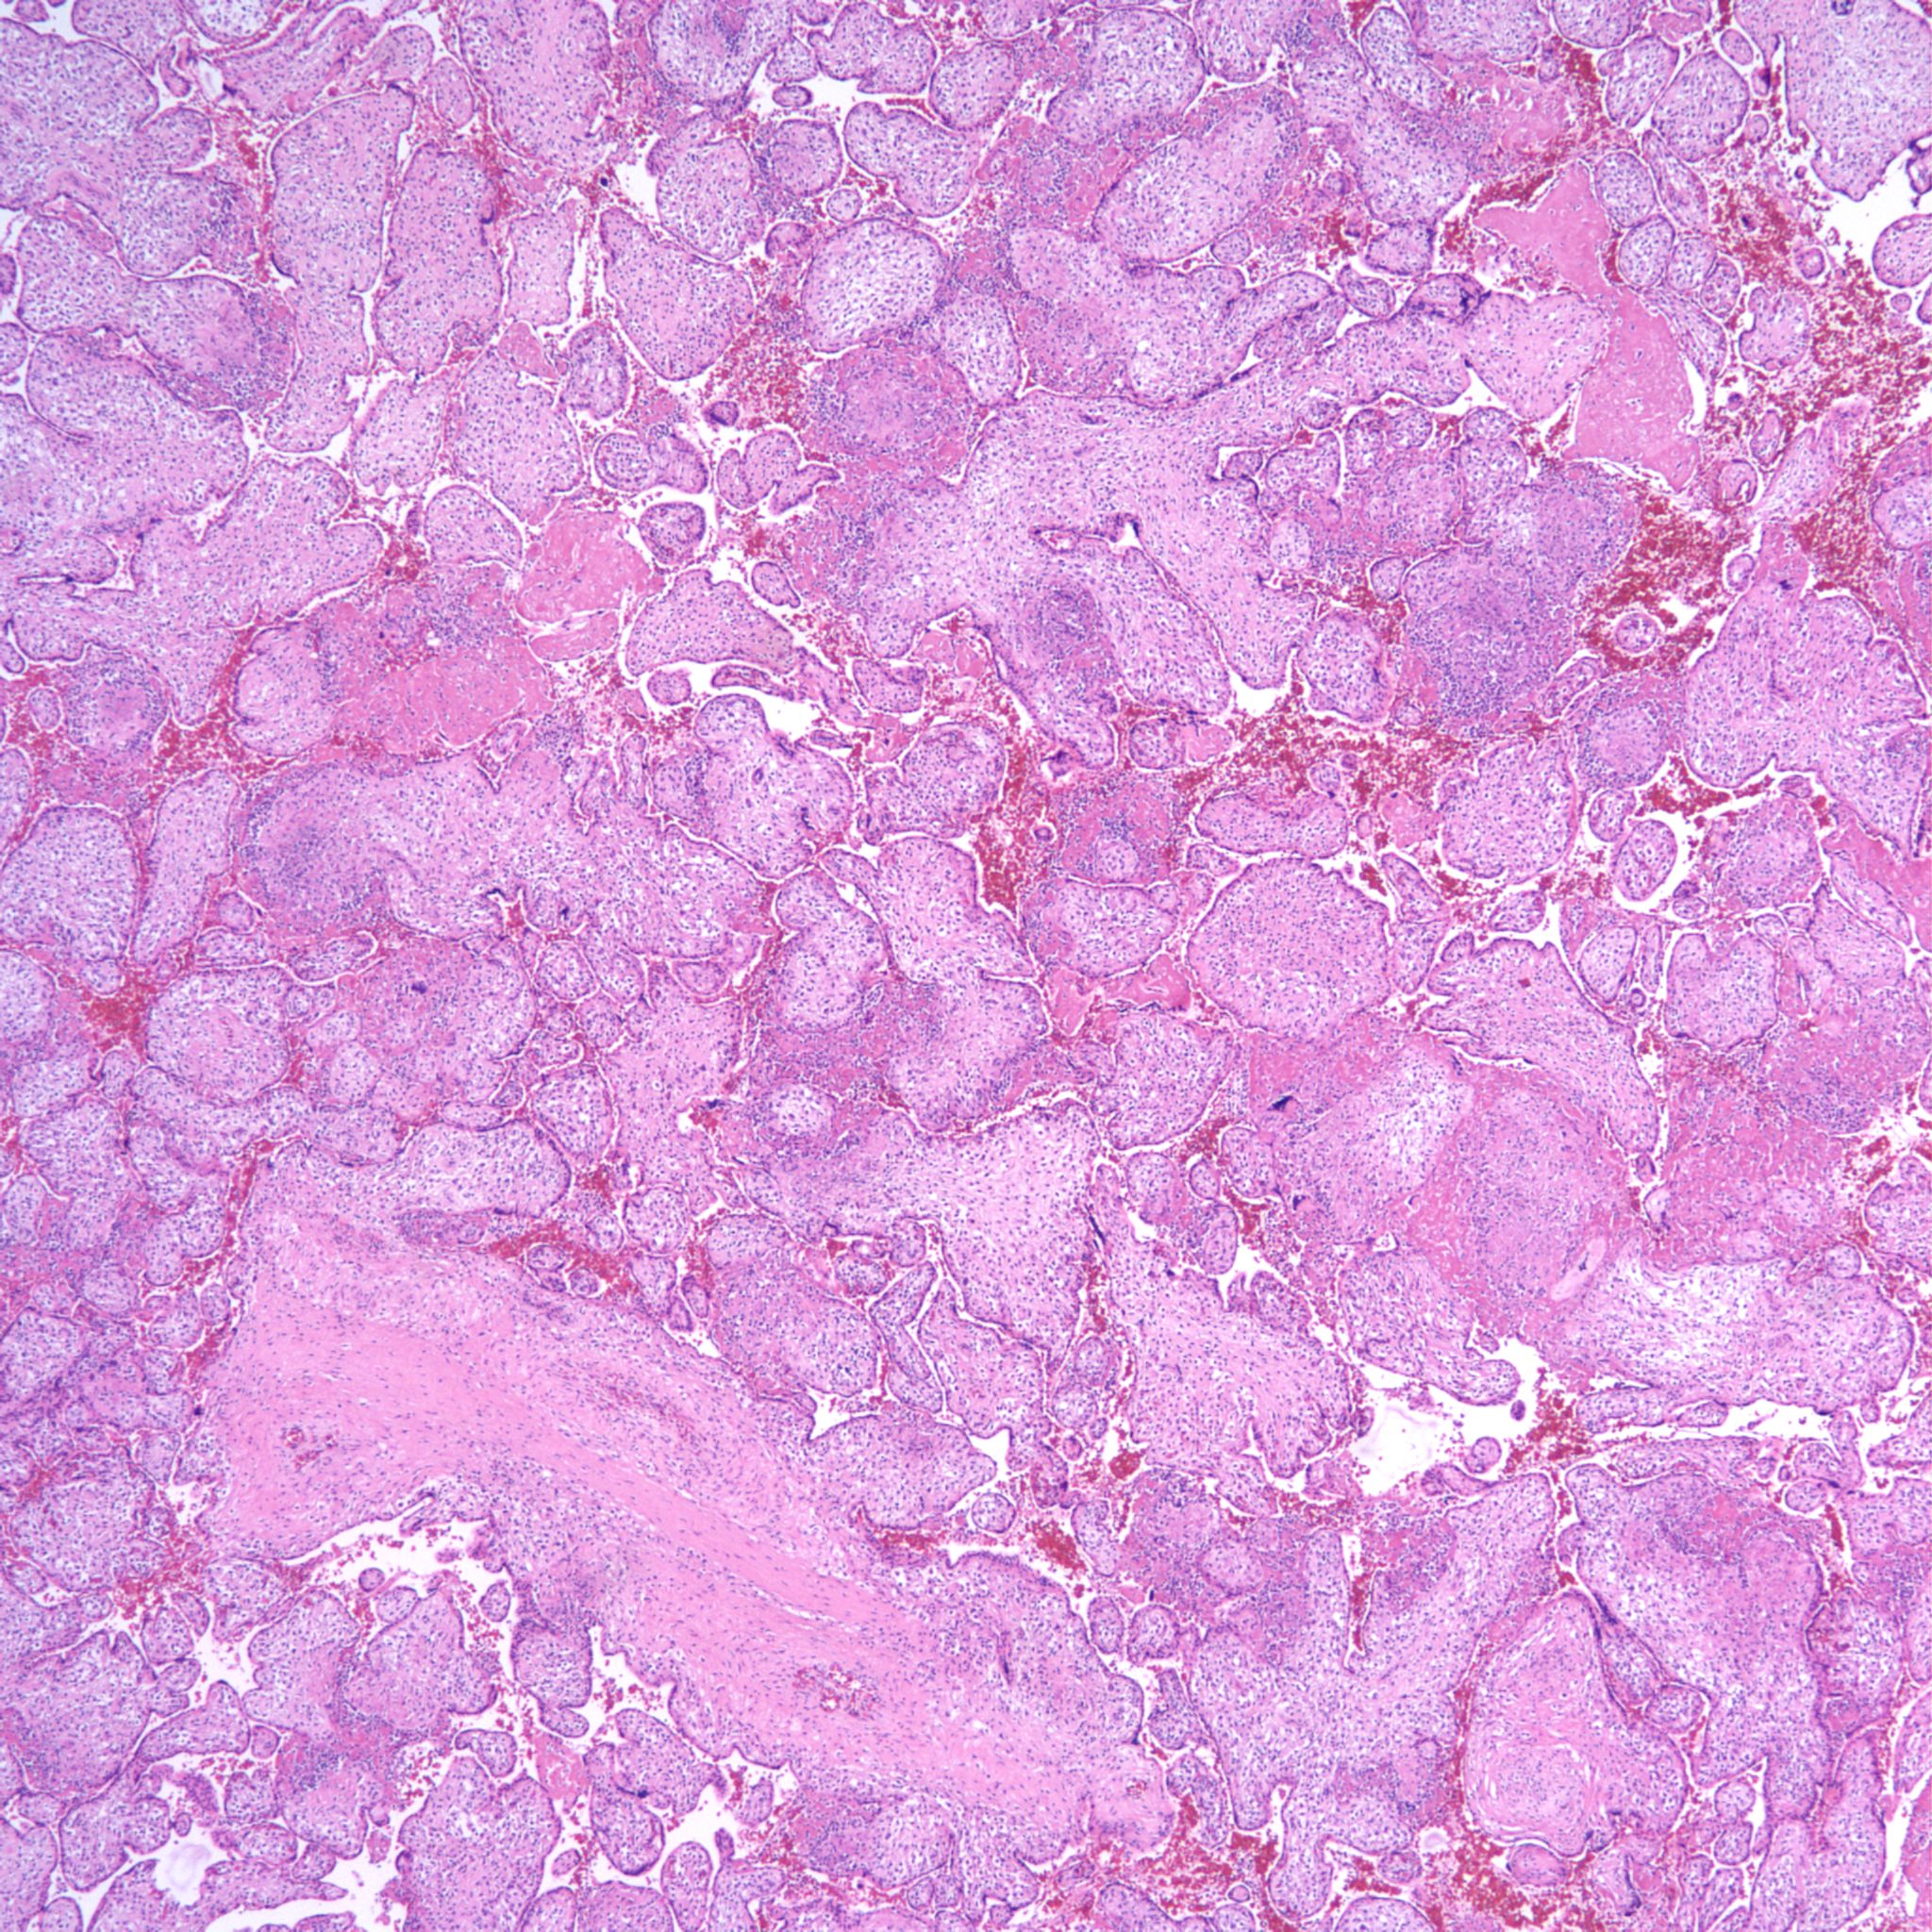

High Grade (massive) CHIV

CHIV with prominent perivillous fibrinoid deposition

CHIV associated with Villitis of Uknown Etiology (VUE)

This pattern could be due to a primary cause of VUE with incidental chemotaxis of monocytes, two pathogenetically interrelated processes, or an incidental focus of VUE in a predominant CIIV disease. Currently, describing the extent of each process and its colocalization or lack of may prove useful until a better way to classify the co-existing lesions can be developed. One study has shown that there is a dichotomy between cases with c4d staining and those without c4d staining18.